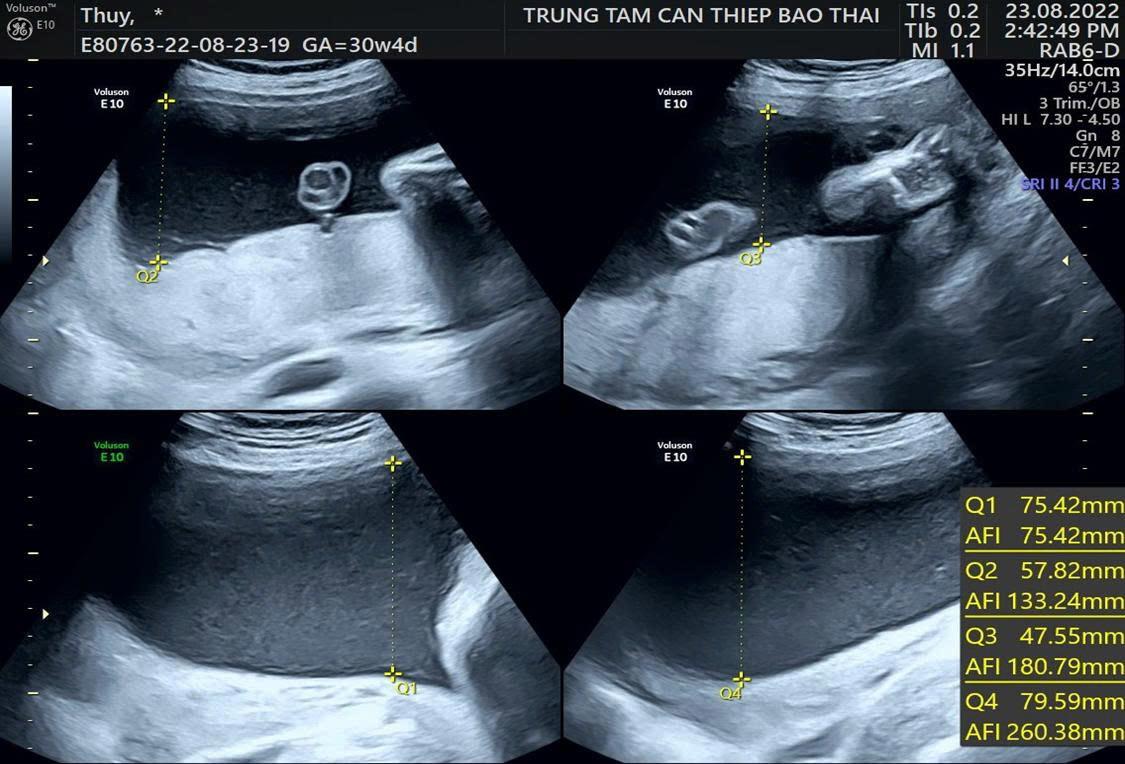

Đa ối được xác định khi chỉ số ối AFI ≥ 25 cm hoặc góc ối sâu nhất MVP ≥ 8 cm trên siêu âm. Đa ối được phân loại theo mức độ dựa trên chỉ số nước ối AFI: nhẹ (25–30 cm), trung bình (30,1–35 cm) và nặng (>35 cm).

Trung tâm Y học Bào thai PhenikaaMec còn đầu tư hệ thống trang thiết bị hiện đại nhằm hỗ trợ xử lý những tình huống phức tạp từ rất sớm. Máy siêu âm GE Voluson Expert 22 cho phép khảo sát mạch máu và dị tật chi tiết; công nghệ giải trình tự gene giúp bóc tách nguy cơ di truyền; hệ thống nội soi túi phôi mở ra cơ hội phát hiện bất thường hình thái học ngay ở giai đoạn đầu thai kỳ. Đây là những công cụ thiết yếu để bác sĩ ra quyết định đúng thời điểm – yếu tố sống còn trong các ca dọa sinh non, hội chứng truyền máu song thai hay đa ối – thiểu ối.